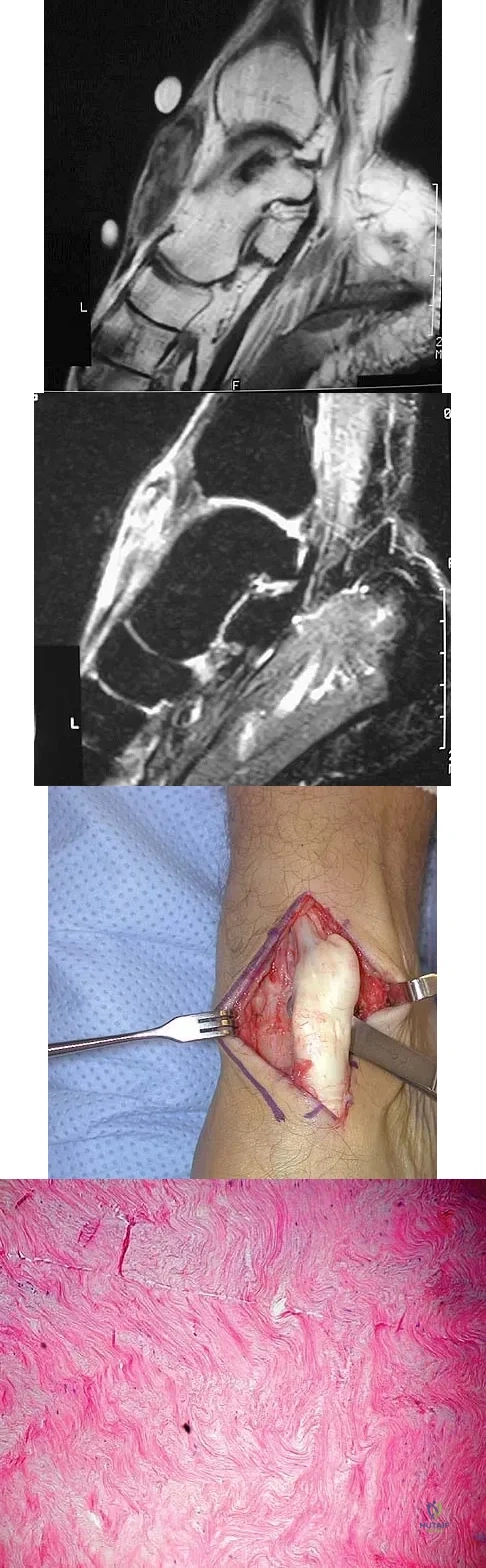

A 40-year-old man has a palpable mass over the dorsum of the ankle. He reports no history of direct trauma but notes that he sustained a laceration to the middle of his leg 6 weeks ago. Examination reveals a 4-cm x 1-cm mass. T1- and T2-weighted MRI scans are shown in Figures 12a and 12b. An intraoperative photograph and biopsy specimen are shown in Figures 12c and 12d. What is the most likely diagnosis?

Explanation